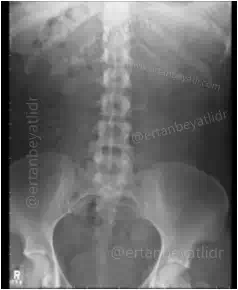

ADBG filmi dik durarak ayakta çekilen karın grafisidir. Genelde acil durumlarda çekilir örneğin: böbrek sancısı (Renal Kolik), Barsak Tıkanması (İleus, Sub-ileus, Volvulus), Barsak ve Mide Delinmesi (perforasyon), Apandisit, intesusepsiyon, Yabancı Cisim yutulması veya makattan sokulması.

Çekim sonrası, ADBG yorumlanması çok önemlidir. Özellikle travmaya bağlı hava sıvı seviyesinin tespiti, bağırsak tıkanmaları, gazların ve yumuşak dokudaki anormal yapıların gözlemlenmesi amacı ile çekilir. Latince’de standing direct abdominal radiograph olarak yazılır.

Çekim ayakta ve P-A (Arka-Ön) pozisyonunda yapılmalıdır.Hastanın karnı statife değmelidir. Diyafram kubbelerinide kesmeyecek ölçüde kaset (35X43) veya dedektör seçimi yapılmalıdır. Tüp kaset mesafesi 100 cm olmalıdır. Santralizasyon iliak kanadın 5 cm üzerine filme dik olacak şekilde yapılmalıdır. Hasta pozisyonu ayarlanıp gerekli ölçülerde kolimasyon yapıldıktan sonra hastaya derin bir nefes alıp tutması (inspiryum) söylenir. Ortalama bir erişkin için 100 KV ve otomatik MaS ile çekim yapılabilir.